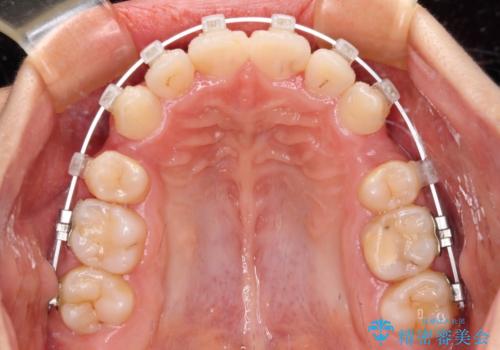

- 咬み合わせと、前歯のデコボコや八重歯、飛び出した口元を気にして来院された患者様です。

上顎は歯列不正が強く、右側臼歯部の咬み合わせは歯1本分ずれている状態でした。

補助装置を用いて奥歯の咬み合わせを改善しながら歯列を後方に移動させ、上下左右第一小臼歯を4本抜歯することで八重歯や口元の突出感を改善することとしました。

奥歯の咬み合わせの不正が顕著であったため、表側のワイヤー装置を選択して矯正治療を行うこととしました。